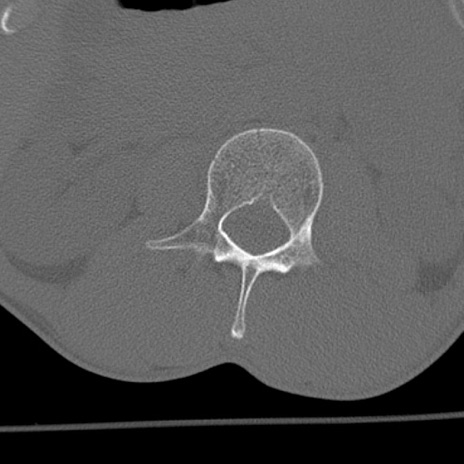

症例3 腰椎CT(横断像)

腰椎CT